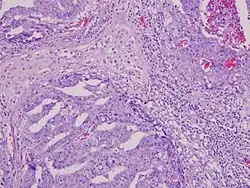

Micrograph (high magnification) of a seminoma. H&E stain.

Mixed germ cell tumor containing embryonal carcinoma, seminoma, and yolk sac tumor. The embryonal carcinoma component (upper left, upper right, and lower left) shows pseudoglandular growth with high-grade features of large, epithelioid, anaplastic cells with prominent nucleoli, indistinct cell borders with nuclear overlapping, pleomorphism, and frequent mitoses. The seminoma component (upper center) shows large, round-polyhedral cells with distinct cell membranes, abundant clear/watery cytoplasm, large central nuclei, and prominent nucleoli. The yolk sac component (lower right, hugging the embryonal component) exhibits microcystic/reticular growth pattern.[26]